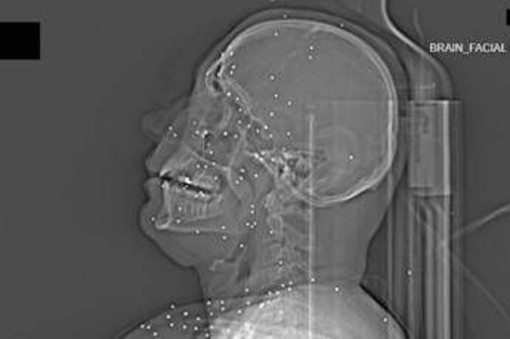

Il volto di Anahita – nome di fantasia, poco più che ventenne – appare come un cielo notturno attraversato da punti luminosi. Piccole sfere metalliche, da 2 a 5 millimetri, disseminate sul viso, nelle orbite oculari, persino nella massa scura del cervello. Sono proiettili “birdshot”, pallini da caccia sparati da un fucile a pompa. A distanza ravvicinata, spiegano gli esperti, non sono affatto “meno letali”: possono frantumare ossa, devastare tessuti molli, perforare facilmente un bulbo oculare. Anahita ha perso almeno un occhio, forse entrambi.

Quell’immagine non è un caso isolato. Fa parte di oltre 75 set di esami diagnostici provenienti da un singolo ospedale di una grande città iraniana, raccolti nel corso di una sola serata, durante la stretta repressiva di gennaio. Una concentrazione temporale che, già di per sé, racconta una dinamica da “mass casualty”, evento con numerose vittime simultanee, tipico degli scenari di guerra o dei grandi disastri.

Accanto ai colpi di grosso calibro, emerge con forza un altro elemento: l’uso sistematico dei pallini metallici. L’Iran è tra i pochi Paesi in cui le forze di sicurezza impiegano birdshot metallico. A lunga distanza, i pallini si disperdono e colpiscono indiscriminatamente. A distanza ravvicinata, diventano devastanti: decine, talvolta centinaia di micro-proiettili che penetrano simultaneamente nei tessuti.